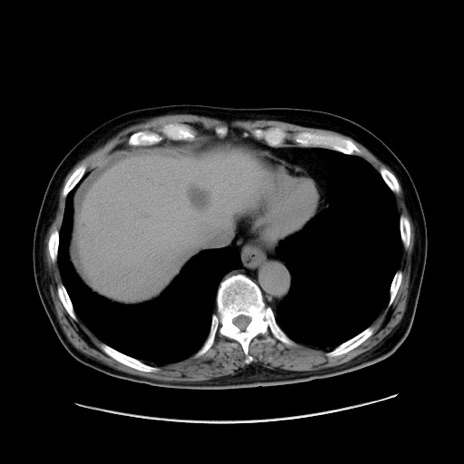

症例30(横断像)

【症例】80歳代男性

【主訴】臍周囲痛

【現病歴】約6時間前から臍下部痛が出現。次第に腹部膨隆・背部痛も生じてきたため来院。背部痛の場所は変化しない。

【身体所見】意識清明、BT 36.3℃、BP  131/87mmHg、P 87bpm、SpO2 100%(RA)、臍周囲自発痛・圧痛あり、反跳痛なし、自発痛部位に一致して板状硬あり、腹部膨隆、腸雑音減弱、CVA tenderness両側陰性。